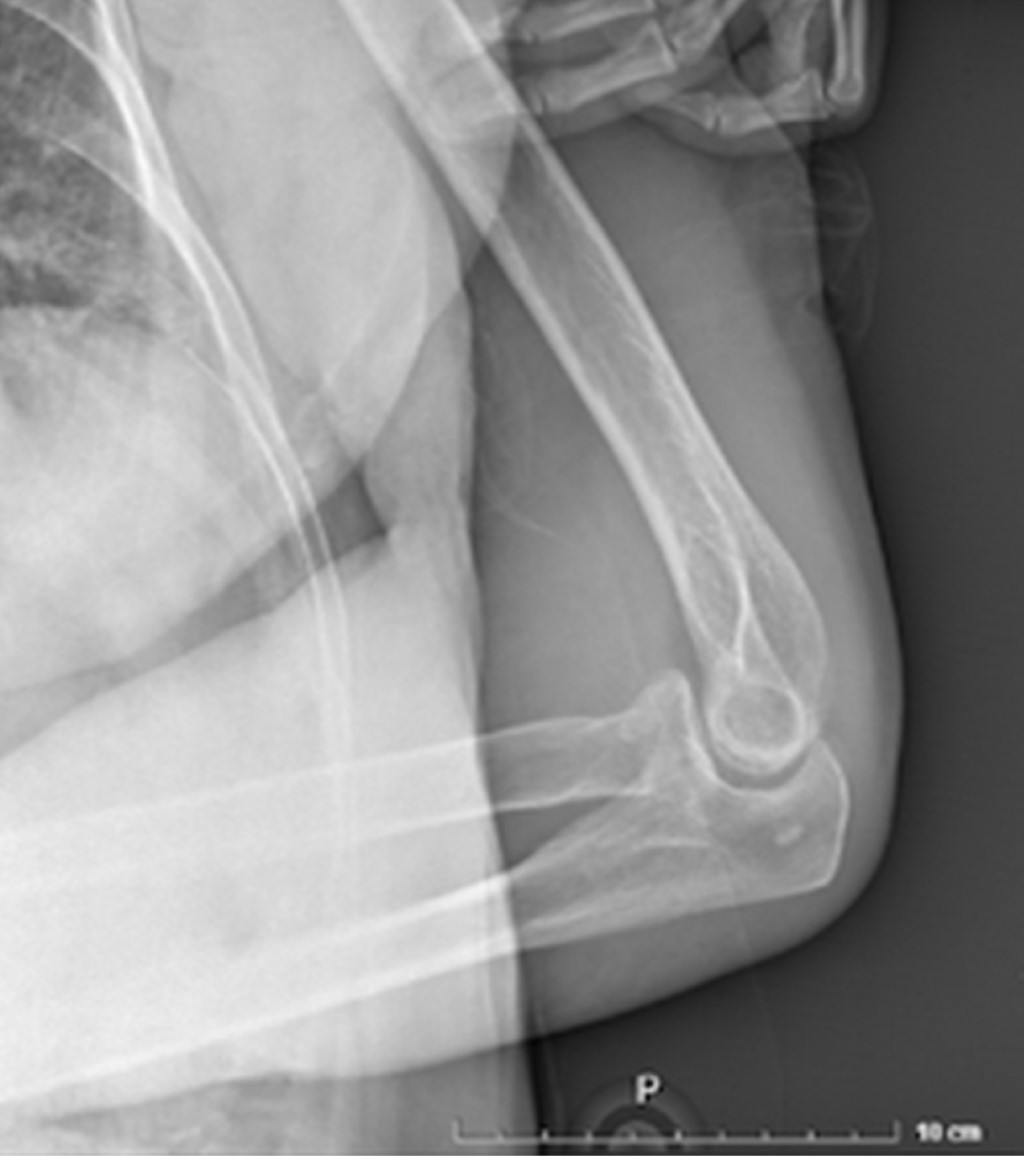

Paciente femenino de 86 años es traída al servicio de urgencias tras caída desde su propio plano de sustentación. El motivo de consulta era dolor en hombro izquierdo y codo ipsilateral. En la exploración física se observaba deformidad en codo y a paciente con miembro torácico por encima de la cabeza, siendo sostenido por extremidad contralateral para disminuir el dolor. La extremidad torácica izquierda se encontraba en abducción máxima y la paciente no era capaz de aducir el hombro. La cabeza humeral era palpable en el borde inferior de la axila. A la exploración neurovascular no se encontraron datos que sugirieran lesión. Radiografías de codo y hombro en proyección anteroposterior y lateral mostraron luxación inferior del hombro (Figuras 1 y 2), así como luxación posterior del codo sin lesión ósea asociada. Ambas lesiones fueron manejadas en quirófano mediante reducción cerrada con paciente bajo sedación. La luxación inferior del hombro fue reducida mediante tracción-contra-tracción del húmero con posterior aducción del hombro. La articulación del codo fue reducida mediante tracción axial con la muñeca en supinación con posterior flexión. Se realizó exploración neurovascular al término donde no se observaron lesiones. Se obtuvieron radiografías de control que evidenciaron correcta localización de la articulación del codo (Figuras 3 y 4) así como de la cabeza humeral (Figura 5). Debido a la mejoría, la paciente fue egresada con férula a 90o e inmovilizador de hombro, iniciando rehabilitación a las 2.5 semanas con movimientos pasivos pendulares de hombro y movimientos de flexión y extensión de codo. El seguimiento se da en la consulta externa a las cuatro semanas, tres y seis meses evolucionando de manera favorable con reincorporación completa a sus actividades de la vida diaria.

Figura 1

Figura 2